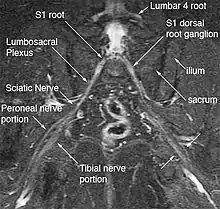

| Deep gluteal space anatomy | |

Anatomy

The hip has five external rotators: The piriformis, superior gemellus, obturator internus, inferior gemellus, and quadratus femoris. The inferior gluteal nerve/artery, sciatic nerve, posterior femoral cutaneous nerve, obturator internus nerve, superior gemellus nerve, quadratus femoris nerve, and inferior gemellus nerves run exit the greater sciatic foramen underneath the piriformis.[6]